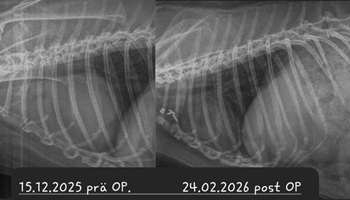

Ein Kaninchen mit Atembeschwerden oder den beschriebenen Augenveränderungen sollte zunächst geröngt werden. Hierdurch lassen sich Verschattungen im Brustkorb schnell und einfach erkennen und es muss anschließend nur noch ermittelt werden, ob es sich dabei um einen Tumor oder eine (reine) Herzerkrankung handelt. Letztere kann zu einem vergrößerten Herzen oder einem Erguss führen, was per Röntgendiagnostik nicht immer von einem Tumor zu unterscheiden ist.

Bei einer Thymom- oder Lymphom-OP handelt sich um einen schwerwiegenden Eingriff, bei dem der Brustkorb des Patienten eröffnet wird und der Tumor möglichst vollständig entfernt werden muss, ohne dabei das benachbarte Herz zu schädigen. Die OP wird nur von wenigen Chirurgen angeboten. Ein Spezialist, der regelmäßig auch Patienten aus Deutschland operiert, ist Dr. Florent Modesto in Brüssel.

Sofern davon auszugehen ist, dass das Kaninchen den Eingriff übersteht und der Tumor sich vollständig entfernen lässt, ist die OP zwar die kostspieligste, aber vermutlich auch die Option mit der besten Prognose

Leider ist trotz allem damit zu rechnen, dass Zellreste des Tumors zurückbleiben und nach einiger Zeit nachwachsen. Je nach Tumor-Art ist dies allerdings mitunter erst nach 3-5 Jahren der Fall - womit das Kaninchen sehr viel Lebenszeit gewonnen hat; hinzu kommt die verbesserte Lebensqualität, nachdem die Masse aus dem Brustkorb entfernt wurde und langfristig auch keine Medikamente gegeben werden müssen.